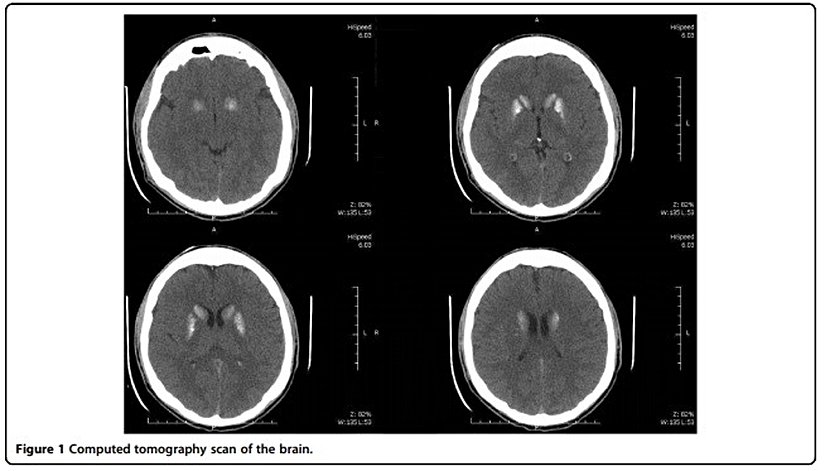

Psikiyatristler uyguladıkları tedaviye cevap almamaları durumunda hastadaki rahatsızlığın fiziksel sebeplerden dolayı ortaya çıkıp çıkmadığını anlamak için kan tahlili, beyin tomografisi, kalp ve diğer organların incelenmesi gibi rutin işlemlere başvururlar. Söz konusu genç hasta için de uygulanan bu rutin tahliller neticesinde oldukça şaşırtıcı bulgular elde ediliyor… Neydi bu bulgular?

- Bilgisayarlı tomografi: beynin orta kısmında bulunan bazal ganglionda magnezyum[1] birikmesi

Beyinde magnezyum birikmesi, kalp atışında ritm bozukluğu, ayaklarda titreme gibi belirtiler arasında doğrudan bir ilişkinin bulunduğundan yola çıkan ve böylece gencin yakındığı rahatsızlığı hipo paratiroidizm olarak adlandıran doktorlar, vücutta magnezyum ve kalsiyum miktarını ayarlayan paratiroid hormonunun (PTH) kanda düşük seviyelerde olması halinde bu hastalığın ortaya çıkabileceği sonucuna varıyorlar.